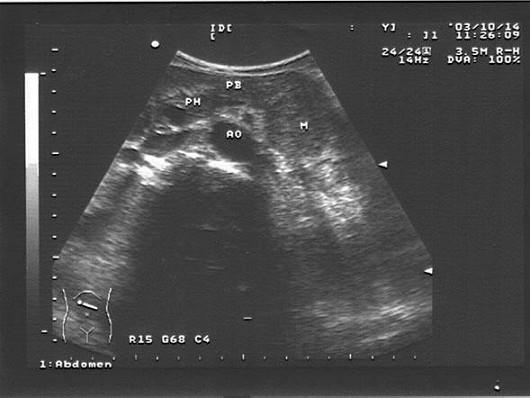

某腹胀患者中腹部声像图表现,最可能的诊断是?(?)A.胰尾癌B.胰腺炎C.胰头癌D.正常图像肿大淋巴结

问题 某腹胀患者中腹部声像图表现,最可能的诊断是?(?)

选项 A.胰尾癌 B.胰腺炎 C.胰头癌 D.正常图像肿大淋巴结

答案 A